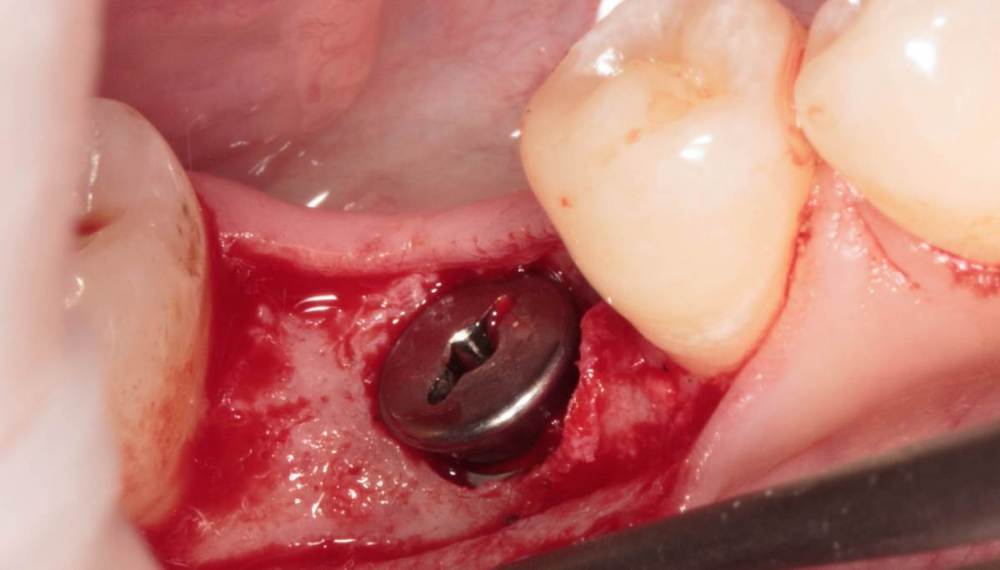

Женька Опубликовано 19 августа, 2023 Поделиться Опубликовано 19 августа, 2023 ?️. Поймал себя на мысли, что испытываю проблемы с ушиванием+ССТ на формике. А именно-не устраивает результат "прирощённой" десны. Вроде на ушивании есть + к объёму, а на протезировании "яма" вестибулярно лишь немного уменьшилась. Подскажите, как лоскут формировать так, чтобы в слоёном пироге имплантат-формик-сст оставался объём слизистой, а не таял. Подумал, что может стоит при имплантации сразу формировать асл. А в кейсе я снова "согрешил" и поставил ультра-низкий формик. В этот раз без всяких послаблений лоскута и натяжения, кмк. Ссылка на комментарий